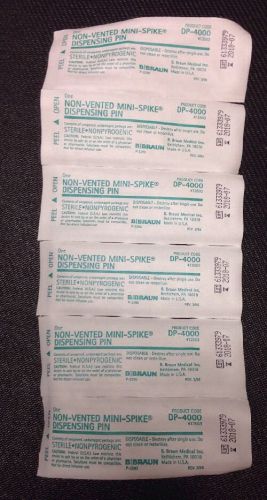

Lot Of 195 B Braun Non-Vented Mini-Spike Dispensing Pin REF:413503 DP-4000